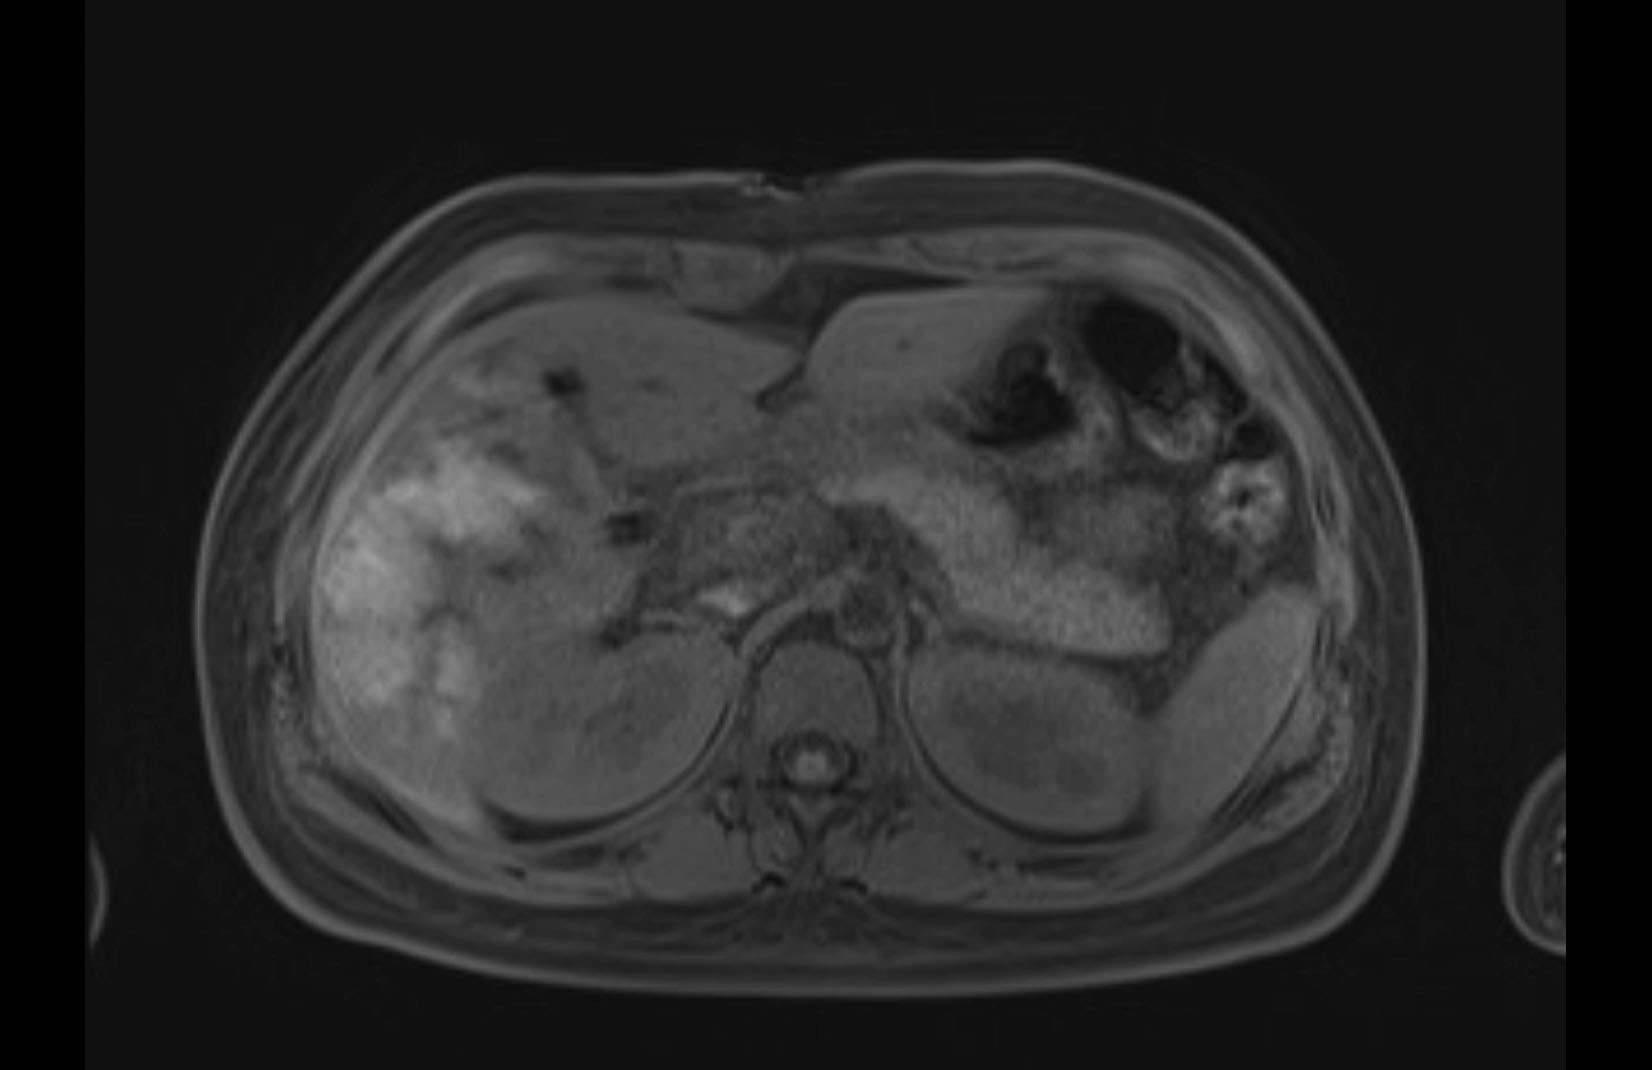

MRI T2

Imaging analysis

Based on initial findings, which issue(s) would you be most concerned about?